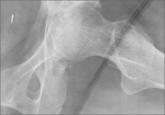

ArticleEikenella corrodens Septic Hip Arthritis in a Healthy Adult Treated With Arthroscopic Irrigation and DebridementAuthor:Gowda ALPublish date: August 28, 2014 We present the case of a seemingly spontaneous septic hip arthritis in a patient with no pertinent medical history. Our patient presented with per...Read More